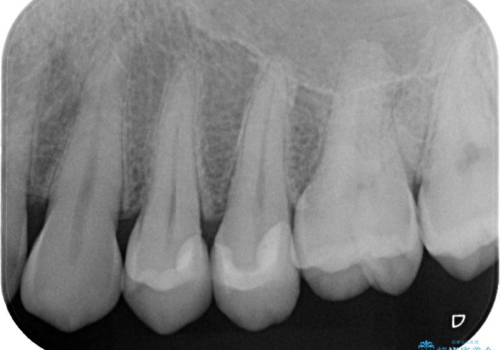

- ホワイトニング希望で来院された患者様ですが、口腔内をチェックしたところ2歯虫歯が見つかりました。無症状ではありましたが、レントゲン画像でも歯髄(歯の神経が内蔵されている場所)近くまでの広がりが確認できました。ランクの高い材料で治療したいとのご要望もあり、変形の少ないシリコン材料を使用した、生体親和性の良いセラミックインレーにて治療を完了しました。術後も症状等なく経過良好です。